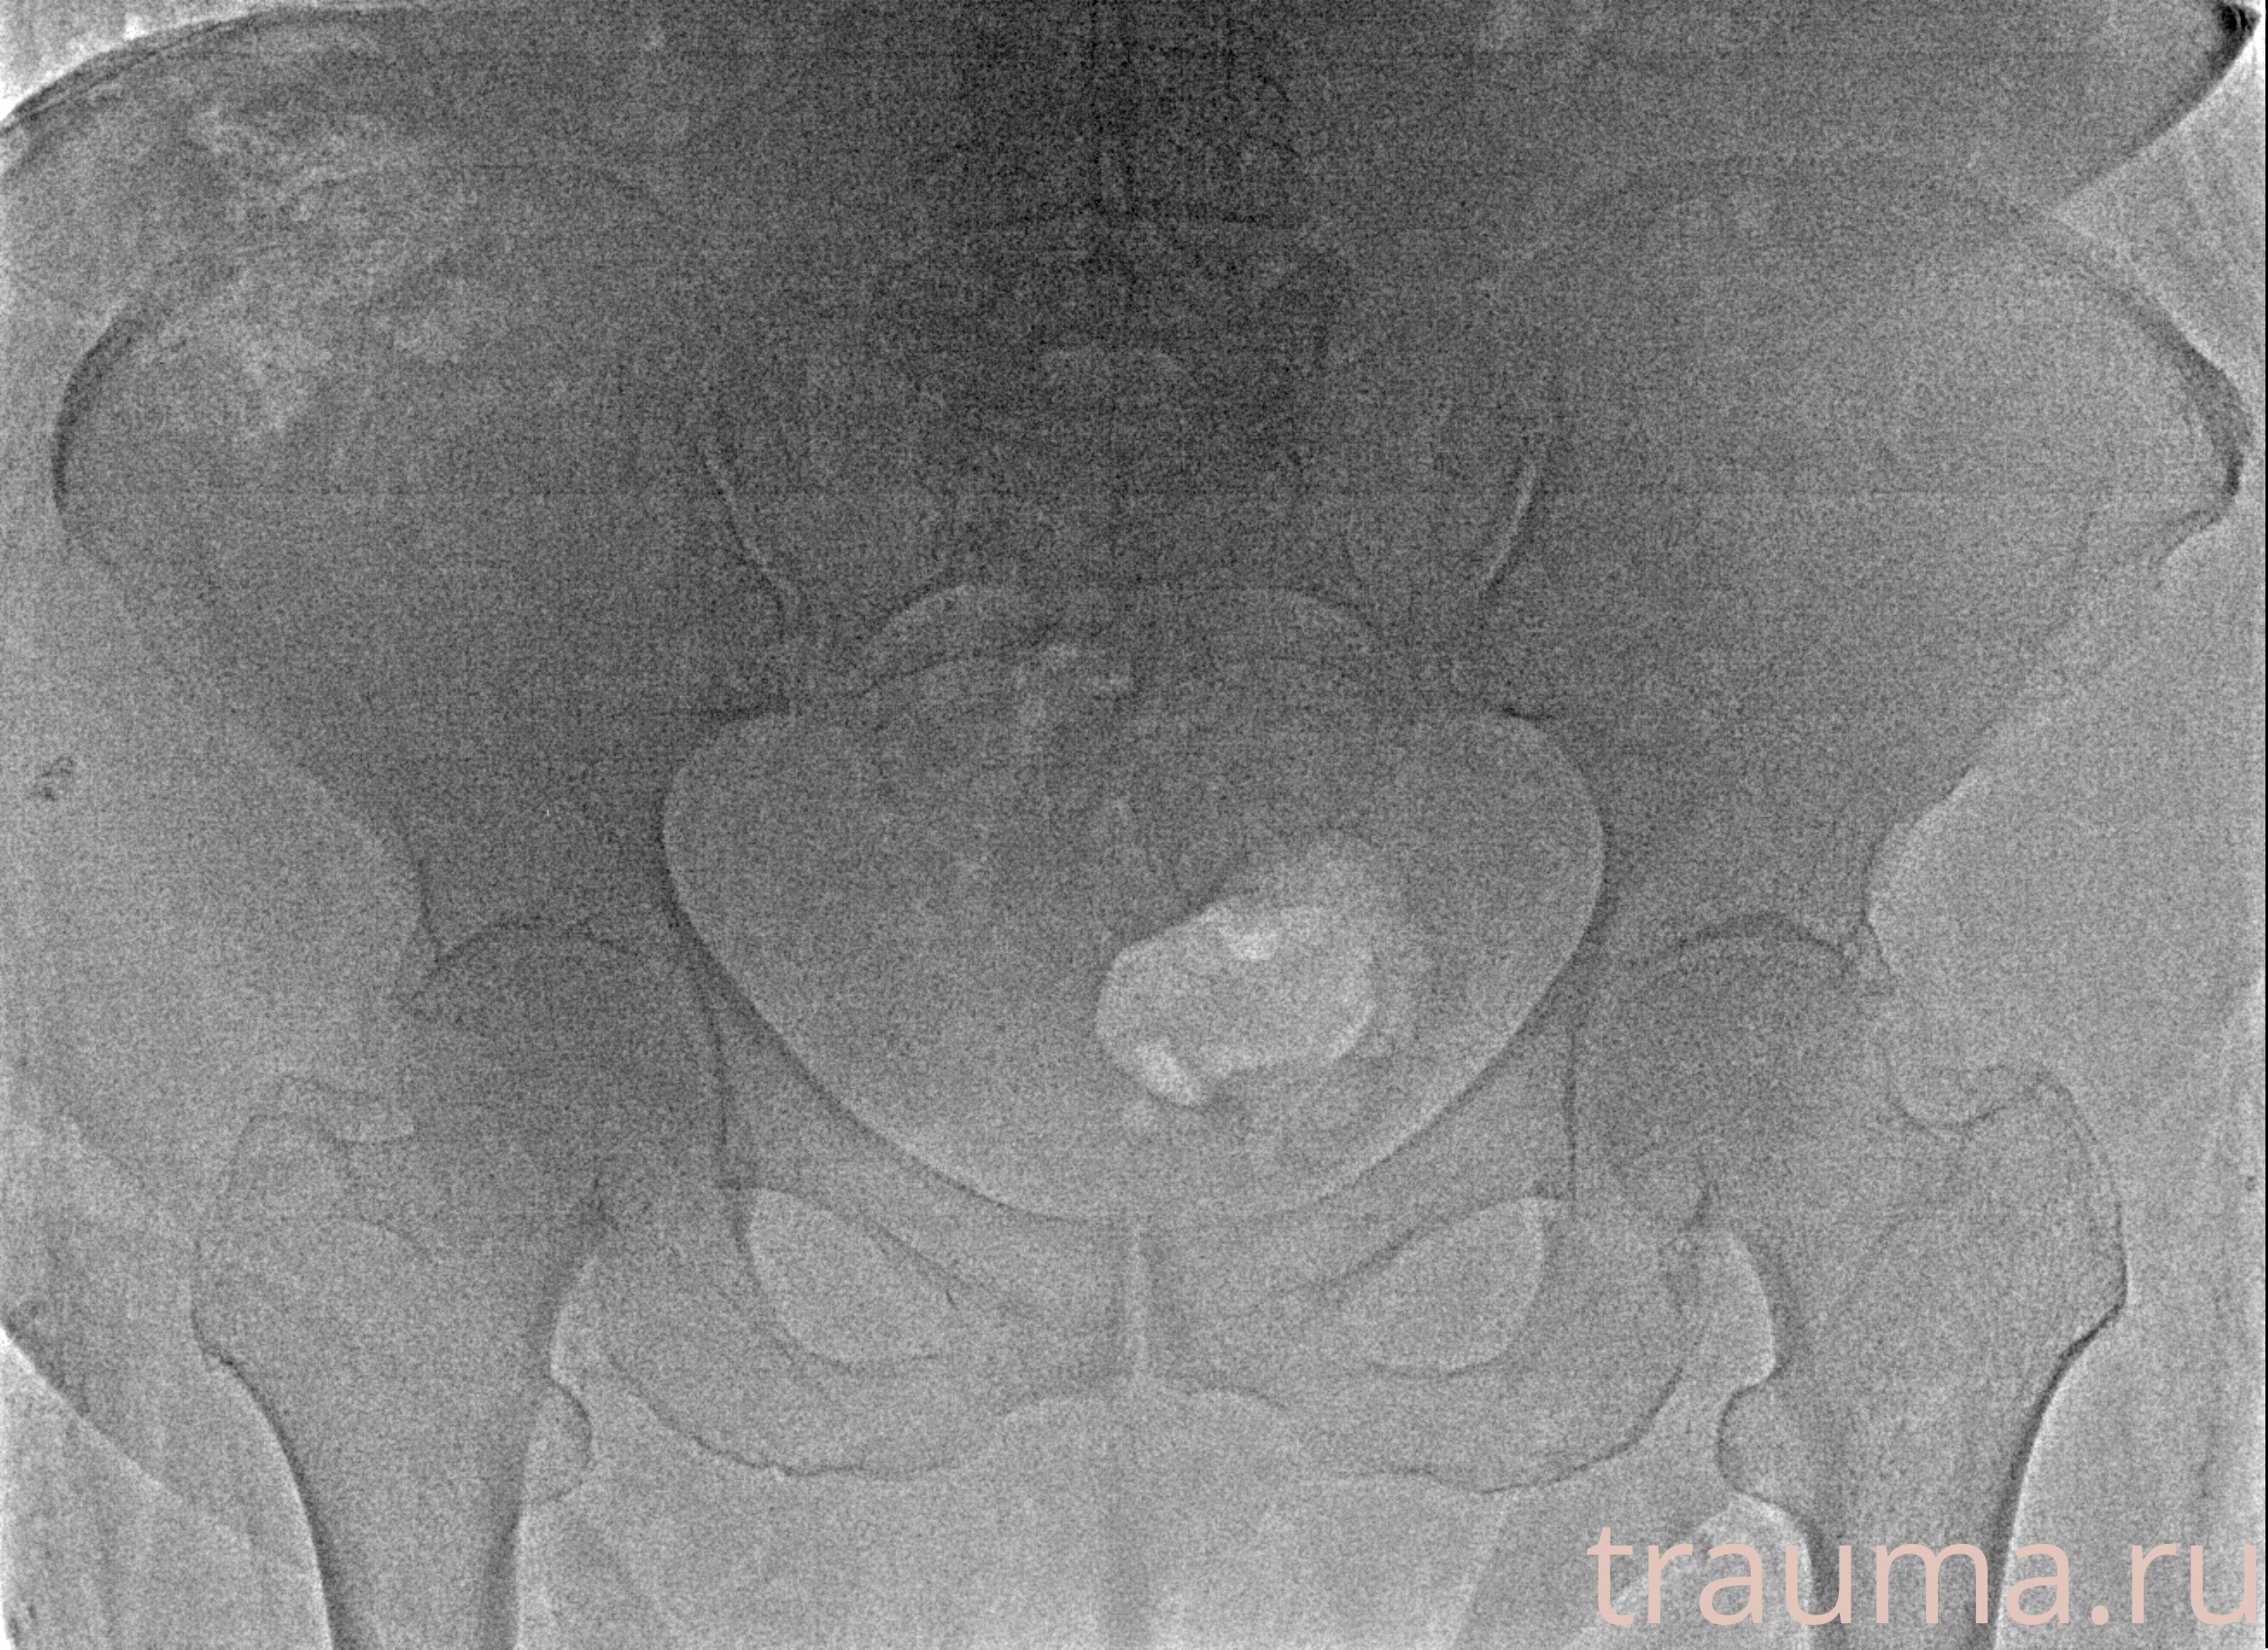

Рентген на дому: по вашему адресу приезжает врач-рентгенолог, травматолог-ортопед с мобильным рентгеновским аппаратом, проводит диагностику травмы или заболевания, делает необходимые рентгенограммы, дает рекомендации по дальнейшему лечению. Получить качественные снимки в домашних условиях возможно благодаря уникальной методике, разработанной МосРентген Центром для института  Склифосовского